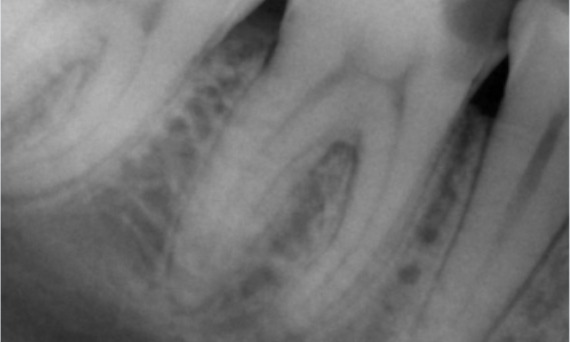

Avant : Radiotransparence périapicale associée principalement à la racine distale et à la perte de la lamina dura sur la racine mésiale.